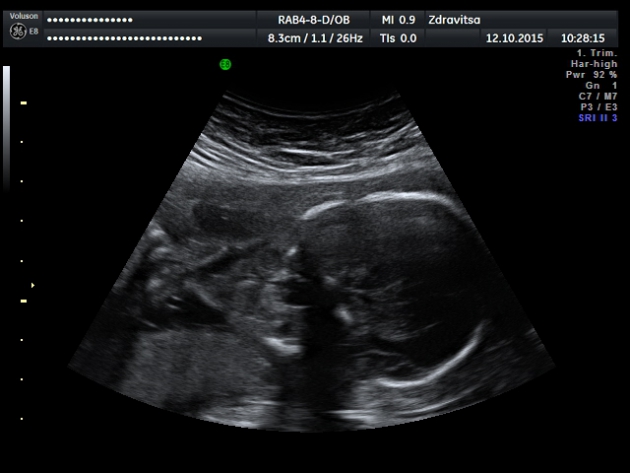

Медведев по этой патологии пишет: "По нашему мнению, наиболее действенной схемой диагностики атрезии пищевода является прямая визуализация пищевода плода в случаях обнаружения необъяснимого многоводия и микрогастрии или отсутствии эхотени желудка".

А так да, очень похоже на атрезию пищевода с трахеопищеводной фистулой.

В заключении по этому плоду в описательной части я указала, что данная структура связана с актом глотания плода. Может быть это и глотка, но что то она большая, пусть лучше будет еще одно мнение ,чем пропущу порок. И еще насторожило то ,что через два дня она вообще ни как не изменилась. Женщине все объяснила, в том числе, что это м.б и вариантом нормы.